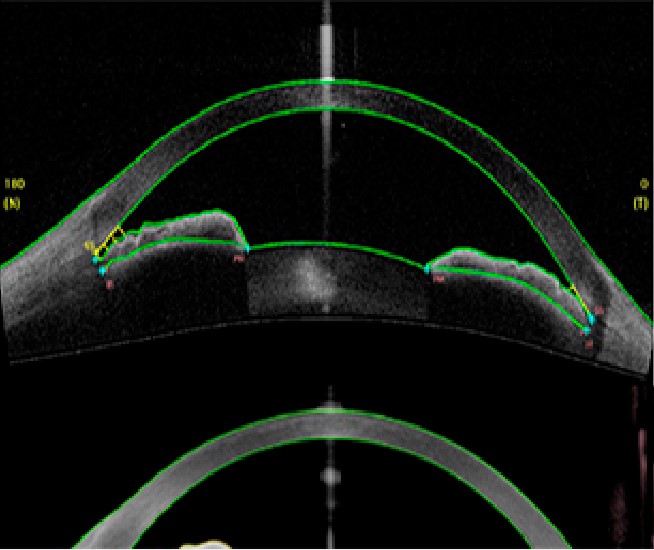

Estudia la anatomía y las capas de la córnea, además de las alteraciones ultraestructurales